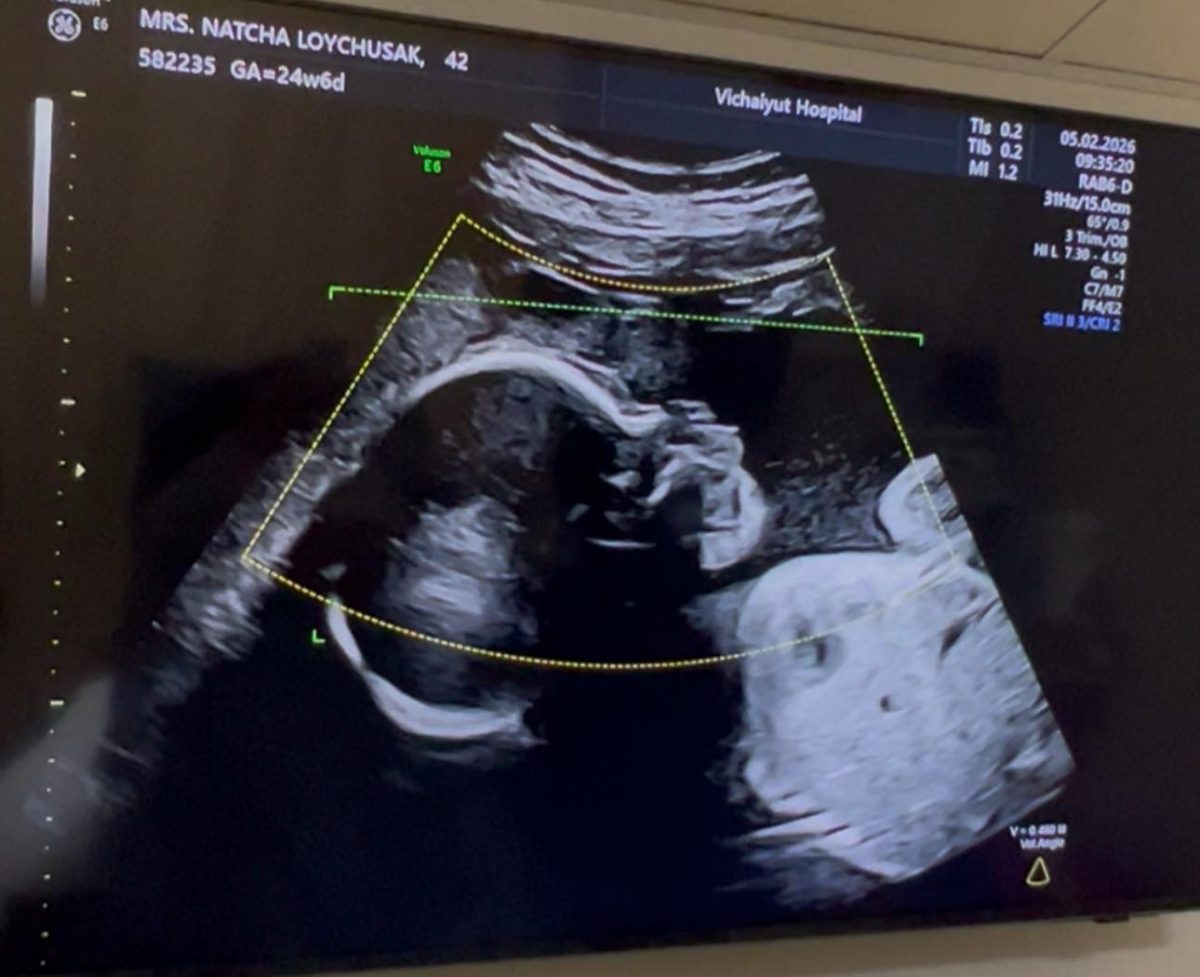

จากภาพอัลตราซาวด์เผยให้เห็นเค้าโครงใบหน้าของ น้องมีเมตตา อย่างชัดเจน นอนยิ้มหวานละมุน แถมจมูกโด่งสะดุดตา เรียกได้ว่าน่ารักน่าชังตั้งแต่อยู่ในท้อง โดย พ่อเจมส์ เขียนแคปชันด้วยความเอ็นดูว่า “แม่หนูมีเมตตาของฉัน จมูกโด่ง ยิ้มหวาน” พร้อมอัปเดตว่า คุณหมอกล้วย แพทย์ผู้ดูแลครรภ์ครูก้อย ยืนยันว่าลูกน้อยแข็งแรงสมบูรณ์ พัฒนาการเป็นไปตามเกณฑ์ทุกด้าน ก่อนจะปิดท้ายด้วยมุกขำ ๆ สไตล์คุณพ่อว่า “สินค้าเด็กเข้าได้เลยครับ ( ฮาาา…. )” ทำเอาแฟน ๆ เข้ามากดไลก์และคอมเมนต์ชื่นชมความน่ารักของ น้องมีเมตตา อย่างล้นหลาม

ด้านคุณแม่คนสวย ครูก้อย นัชชา ก็ไม่น้อยหน้า โพสต์คลิปอัลตราซาวด์ของลูกสาวเช่นกัน พร้อมแคปชันสั้น ๆ ว่า “แม่ว่า…ดูทรงยาว ทรงคมนะ” งานนี้หลายคนอดเดาไม่ได้ว่า น้องมีเมตตาน่าจะได้ความสูงยาวและเค้าโครงคม ๆ มาจากพ่อเจมส์และแม่ก้อยแบบเต็ม ๆ

ก่อนหน้านี้ ครูก้อยเคยให้สัมภาษณ์ว่า การตั้งครรภ์ครั้งนี้แพ้ท้องน้อยมาก อารมณ์ดี มีความสุขตลอด เนื่องจากมีการเตรียมความพร้อมอย่างรอบด้านตั้งแต่ก่อนตั้งครรภ์ ทั้งการจัดการเรื่องงาน โภชนาการ และการออกกำลังกาย เนื่องจากมีภาวะมีบุตรยากจึงมีความเตรียมความพร้อมเป็นพิเศษ เมื่อทุกอย่างลงตัวก็ส่งผลให้ลูกน้อยในท้องอารมณ์ดีตามไปด้วย จนเห็นได้จากภาพอัลตราซาวด์ที่น้องมีเมตตานอนยิ้มหวาน น่าเอ็นดูตั้งแต่อยู่ในท้อง